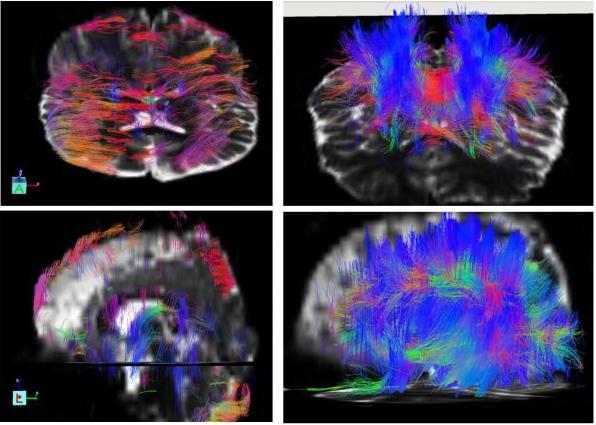

腦立體定向技術(shù)起源于上世紀(jì)60年代,發(fā)展至今已非常成熟。同時手術(shù)的 神經(jīng)調(diào)控靶點、手術(shù)的入路及方案、術(shù)后管理等都是經(jīng)過了幾十年的探索和總結(jié)而不斷完善來的,被證實是完全安全有效的靶點。以往早期的腦立體定向技術(shù)設(shè)備比較簡單,都是徒手定位,誤差基本都在10mm-13mm,如今為了確?;颊咝g(shù)后各項指標(biāo)正常和手術(shù)過程的安全,我們引進的第五代腦立體定向技術(shù)采用的是DTI+CT+MRI影像學(xué)技術(shù)融合定位的方式,做到實時的、可視化、個體化的數(shù)字精¨確定位,其定位誤差也從以往的10-13mm縮減到如今的±0.01mm。